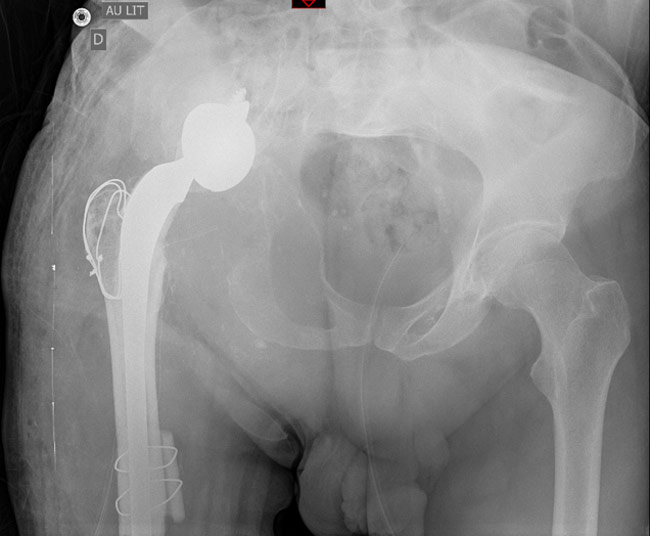

A hip revision with a stemmed cup (transtrochanteric approach for gluts) and Allograft Prosthetic Composites was performed.

A hip revision with a stemmed cup

A Lagrange and Letournel femoral cemented stem was implanted